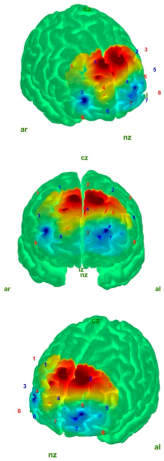

| Control | AIS | |

|---|---|---|

| EO |  |  |

| EC |  |  |